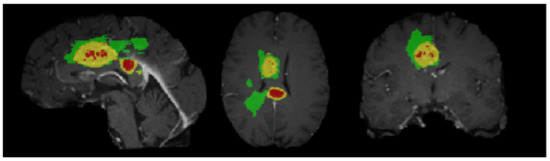

4.2. Segmentation Results

5.6.1. Segmentation Boundary Loss